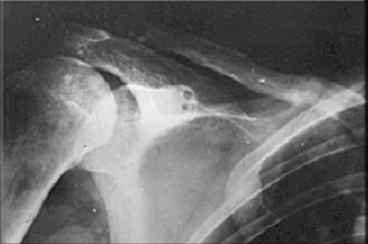

Если заинтересует вариант фиксации трансплантата, представленный в приложении, с удовольствием поделимся опытом.